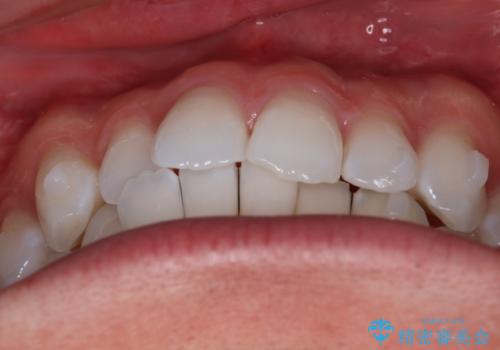

治療について

治療当初は、計画通りに治療が進むか心配でしたが、しっかりマウスピースを使用していただいたことで

治療期間も長引くことなく歯並びを綺麗に改善することが出来ました。

患者様の希望もあり、前歯の微調整で1回リファイメント(マウスピースの再発注)を行いました。

患者様の希望に沿う治療を提案することができ良かったと思います。